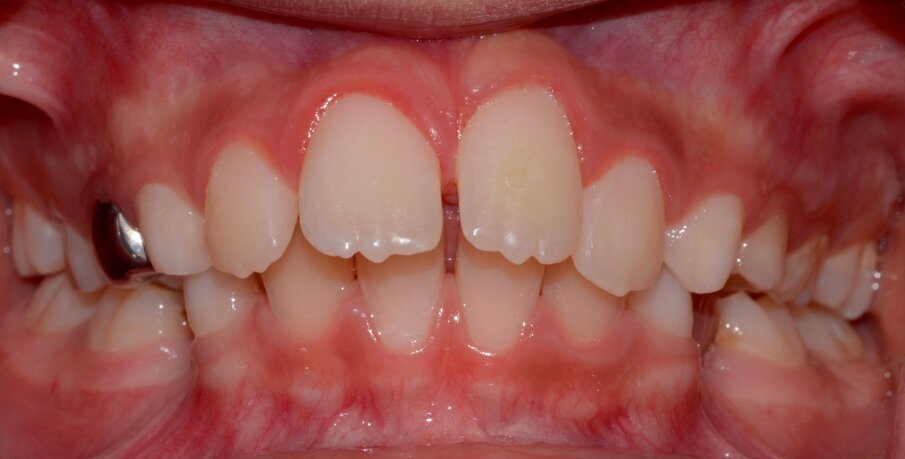

An 8-year old child presented to the department of paediatric dentistry at the Hamdan Bin Mohammed College of Dental Medicine (HBMCDM) at the Mohammed Bin Rashid University (MBRU) in Dubai Healthcare City. He allegedly fell off a climbing wall, and knocked out his upper left maxillary incisor (tooth # 21) and cut his lower lip (Figures 1 and 2). This occurred at 14:15 hours at school, and the school nurse called the patient’s mother at 14:20 hours. The patient’s mother asked the nurse to find the tooth and put it in milk. The tooth’s “dry time” was thus around 10 minutes. The patient attended with both his mother and aunt, to our specialist clinic at 14:55 hours.

• Lower lip through- and-through ragged laceration of the lower lip (Figure 1).

Figure 1: Initial presentation. 21 was avulsed and its socket appeared empty. There was a laceration of the lower lip